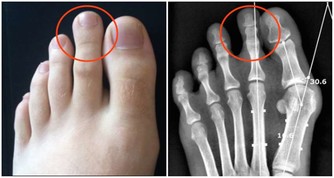

以下圖片來源weixin 4、強化肌肉 適量喝水能夠防止肌肉抽筋,潤滑身體關節。如果體內有足夠的水分,運動的強度可以更大、時間也可以更長,更晚感受到極限,這也有助於練出健美的身材。 5、滋養肌膚 一旦脫水,皮膚上細小的皺紋和紋理將會變深。水是天然的美容霜,喝水能為皮膚細胞補充水分,使它們更飽滿,讓人看起來更年輕。而且水分能夠去除肌膚上的污垢,改善血液循環,使肌膚煥發光彩。 如果在喝水時加上5種食物會有更多的益處哦。